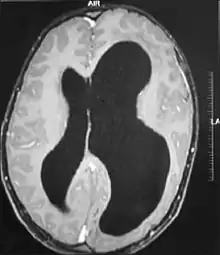

Hemimegalencephaly

Left-sided hemimegalencephaly in a person with neurofibromatosis[8]

Hemimegalencephaly is an extremely rare form of macrocephaly and is characterized by uneven development of brain hemispheres (one half of the brain is larger than the other).[9] It can present by itself or in association with phakomatosis or hemigigantism. Additionally, hemimegalencephaly will frequently cause severe epilepsy, focal neuro-logical deficits, macrocrania, and mild to severe intellectual disability.[10]